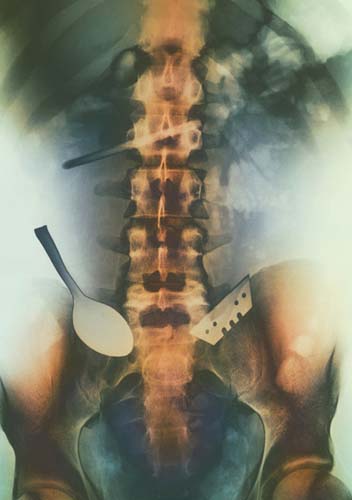

Yutulan jilet ve kaşık hastanın bağırsağına yerleşmiş